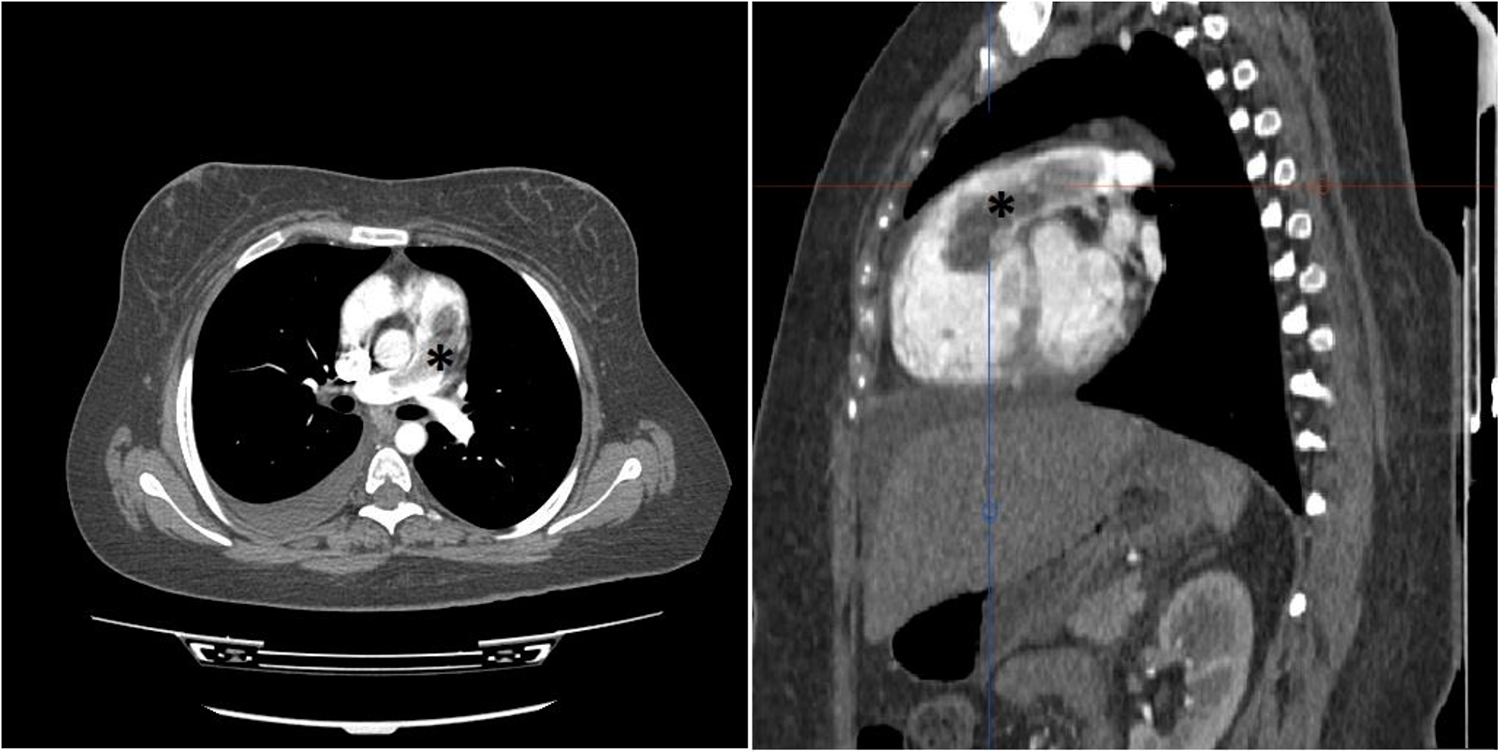

In consideration of the patient's stable clinical status, an immediate computed tomography pulmonary angiography (CTPA) was performed, demonstrating severe RV dilatation with a large defect in the RVOT protruded to PA, while no defects were observed in more distal arterial branches (Figure 1).

Figure 1

Thorax CT study with intravenous contrast in axial (left) and oblique sagittal (right) views shows elongated intraluminal mass and filling defect (*) arising from RVOT with extension to PA trunk. No invasion to myocardium is detected. No intraluminal filling defect in lobar and segmental branches of PA noted. (not shown).